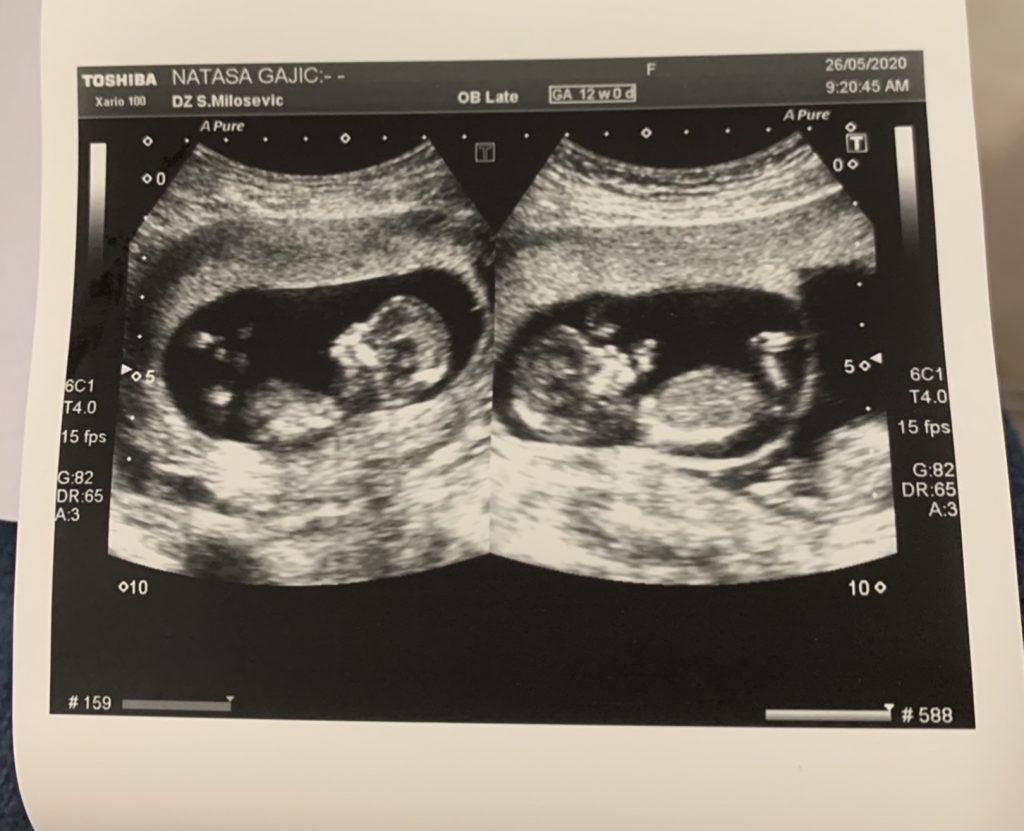

Foto: Privatna arhiva Foto: Privatna arhiva Foto: Privatna arhiva Ispovest porodilje s koronom: Za smrt bebe krivim lekare autor: Milica Čule Hronika 21. nov. 2020. 07:52 > 21. nov. 2020. 15:02 0 Podeli vest: Porodilja Nataša Gajić, koja je u devetom mesecu blizanačke trudnoće, zbog komplikacija izazvanih koronavirusom, ali i lekarskog nemara, izgubila jednu bebu, opisala je za Nova.rs pakao kroz koji je prolazila u zdravtvsenim ustanovama kao kovid-pozitivna trudnica, ali i otkrila zašto za sve što joj se dogodilo, krivi lekare GAK Narodni front. Podeli vest: Oglas Nataša je takođe nakon porođaja bila u izrazito teškom stanju, kao i njena druga beba, ali su srećom, obe uspele da prebrode krizu."U poslednjoj nedelji oktobra počeli su prvi simptomi moje korone, temperatura mi se danima povećavala 37, 38, iz dana u dan, nikako da se spusti. Čula sam se sa doktorom Kikanovićem koji mi je rekao da pijem paracetamol. Međutim, bilo mi je sve gore i otišla sam u Narodni front, jer sam mislila da mi je pukao vodenjak. Urađen mi je ginekološki pregled, CTG i ultrazvuk. Bebe su bile vitalne. Rekli su mi da, obzirom da sam pozitivna trudnica, da idem kući, da se odmaram, da mi nije pukao vodenjak. Bilo mi je sve gore i gore, zvali smo Hitnu pomoć, ali nisu hteli da me voze i rekli su da to nije u njihovoj nadležnosti da voze kovid pacijente. Do "Dragiše Mišovića" pa posle u "Front" sam odvezena kolima Hitne pomoći. Hitna pomoć je na kraju pristala da me odveze jer su shvatili ozbiljnost situacije. Tražila sam da mi daju infuziju, rekli su mi da idem u GAK. Molila sam za infuziju, jer mi nije bilo dobro, a oni su ponavljali da su mi bebe dobro i da nema potrebe. Nisu hteli da čuju, da shvate da meni kao kovid trudnici nije dobro, a ne bebama. Niko mi nije ponudio hospitalizaciju, kako su rekli, da jesu, prihvatila bih. Laž je da su hteli da me hospitalizuju", kaže Nataša Gajić. Nataša Gajić, Foto: Privatna arhiva | Nataša Gajić, Foto: Privatna arhiva Prema njenim rečima, pakao se nastavio narednih dana. Stanje joj je bilo sve gore, a, kako ponovo ističe, niko nije hteo da je primi u bolnicu. Tek kada su joj počele kontrakcije, primljena je u GAK."U Narodni front sam došla oko pola 8 uveče, kontrakcije su mi počele oko 7. Kada sam došla na prijem, uradili su mi samo vaginalni pregled, a bila sam otvorena sedam prstiju, nije mi urađen ni CTG, ni ultrazvuk. Dakle, samo pregled. Da su to uradili verovatno bi otkrili u kom stanju su mi tada bile bebe, možda bih se porodila odmah, ne vaginalno, možda bi život druge bebe bio spasen. Nakon pregleda, rekli su mi da čekam. Stavili su me na krevet, ali taj krevet nije mogao da stane u lift, pa su me poslali da idem peške uz stepenice", kaže Nataša i nastavlja:"Međutim, boks je bio zaključan, a ja sam samo razmišljala o tome da gubim vreme. Tražili su nekoga da otključa boks... Neverovatno. Organizacija na kovid odeljenju u GAK-u je užas. Ja sam tamo stigla u pola 8, porodila sam se oko 10.17 minuta, da su me odmah primili sada bih imala oba deteta u krilu, a ne na Lešću da posipam pepeo jedne bebe", kaže Nataša i navodi da su potom dovezli pokretni ultrazvuk. Suprug Branko i Nataša, Foto: Privatna arhiva | Suprug Branko i Nataša, Foto: Privatna arhiva "Tad su mi rekli da je jednoj bebi stalo srce. Mrtvu bebu sam rodila prvu, jer je zatvarala put drugoj, živoj bebi. Rodila sam je prirodno, bez epidurala, nije bilo vremena za moju paniku, bol i strah", priča Nataša. Ultrazvuk, Foto: Privatna arhiva | Ultrazvuk, Foto: Privatna arhiva Potom navodi da se u boksu pojavio doktor Kikanović, koji je, kako ona tvrdi sve vreme govorio da ona nije njegov pacijent."Samo je došao i pitao me da li sam čula da jedna beba nije živa i otišao. Osoblje se međusobom pogledalo, ni oni nisu verovali da je samo otišao iz boksa, nije bilo ljudski, nije bilo humano", priča ona drhtavim glasom i ističe da je dr Kikanović vodio njenu drugu trudnoću, kada je rodila ćerku Srnu.Nataša Gajić se sada nalazi kod kuće sa bebom koja je preživela."Nika je rođena sa 2 kilograma i 210 grama, sada ima 300. Mala je, ali borbena. Non stop je grlim i mirišem. Ljudi me teše da je druga beba anđeo koji je otišao na nebo odmah. Da sam nosila anđela u sebi...", kaže ona blago jecajući.Za kraj ističe da je njen cilj da se pomogne kovid trudnicama, da ne prolaze kroz ono kroz šta je ona prošla. Slika iz bolničke postelje, Foto: Privatna arhiva | Slika iz bolničke postelje, Foto: Privatna arhiva Inače, Nataša kaže i da na Izveštaju iz Fronta piše da je po prijemu utvrdjena smrt bebe što je orgromna laže,jer je prema njenim rečima po prijemu u porodilište bio odrađen samo vaginalni pregled."Da su tada konstatovali smrt bebe verovatno bi se radio hitan carski rez jer su bebe bile jednojajčane bliznakinje tj. delile su istu placentu. (I samim tim smrt jedne bebe životno ugrožava drugu bebu), Ctg takođe nije urađen- dokazaće se jer slip sa Ctg-a ne postoji. Ultrazvuk po prijemu nije urađen- jer da jeste i da su tad otkrili smrt bebe onda bi isto tako moralo to da se dokumentuje sličicom sa ultrazvuka jer smrt bebe nije mala stvar pa da oni to vide na ultrazvuku a da ne postoji dokaz o tome u vidu slip-a sa ultrazvuka", dodaje Nataša.Tako da kako ona tvrdi to njihovo “po prijemu utvrđena smrt bebe” pada u vodu. Nego su zapravo ona dodaje oni od prijema do porođaja ugrozili tri života!"Moj krajnji cilj ove priče je da svaka buduća pozitivna porodilja zna gde da ide, a ne da traži, zove, moli i juri da sazna gde treba da traži pomoć i kome može da se javi da joj bude pružena medicinska pomoć. Za moj život su se borili 2,5 sata, kažu da su im klompe padale s nogu. Trčali su po klinici da nađu krv, trombocite, ogroman je stres saznanje da su vam se borili za život dva sata, a ne mogu da zamislim koliki je njima stres. Rekali su mi da sam bila sa dve noge u grobu, a onda su mi rekli da 2. novembra slavim kao svoj drugi rođenadan, ali to je za mene i crni dan, jer umesto da sada imam četiri ćerke u krilu, ja imam tri. Znam da je greška bila na prijemu u GAK, u prijemnom odeljenju, tvrdim da mi niko nije ponudio hospitalizaciju tako da nisam ni mogla da je odbijem, a Zlatibor Lončar, ministar zdravlja nam je lično obećao da će da sprovede istragu", završava Gajićeva.***Pratite nas i na društvenim mrežama:FacebookTwitterInstagram Trudnica sa koronom izgubila bebu: "Molio sam da je prime" Društvo 0 Muž porodilje s koronom: Lekari krivi za smrt naše bebe Hronika 0 Moj brat je stradao zbog pogrešnog lečenja dr Jelene Sopta Hronika 0 "Za smrt moje sestre krivi su lekari iz Višegradske" Hronika 0 Policija ušla u Višegradsku posle smrti porodilje Hronika 0 gak korona nataša gajić porodilja Pratite nas na društvenim mrežama: Koje je tvoje mišljenje o ovoj temi? Učestvuj u diskusiji ili pročitaj komentare Budite prvi koji će ostaviti komentar Pošalji komentar Pročitaj komentare (0)